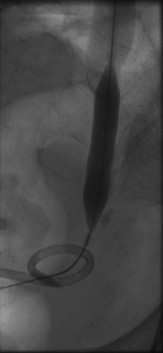

Distal right ureter after dilation and nephroureteral catheterization

Published July 12, 2014 at 163 × 353 in Bilateral insertion of nephroureteral stents after balloon dilation of malignant obstruction of the distal ureters. Ken U. Ekechukwu, MD, MPH, FACP..

Distal right ureter at full balloon inflation